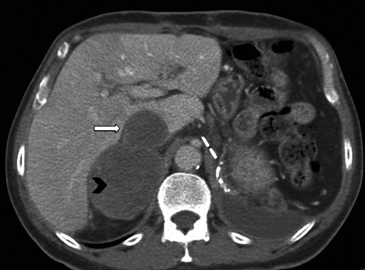

En la TC no contrastada las glándulas suprarrenales normales son homogéneas y simétricas, con una densidad muy similar a la del parénquima renal adyacente (Figura 1 a). Con un medio de contraste ev la glándula suprarrenal se opacifica en forma homogénea, similar al hígado o al bazo (Figura 1 b). Si la cantidad de tejido adiposo retroperitoneal es abundante las glándulas suprarrenales pueden aparecer enteramente rodeadas por grasa y su delimitación es más fácil (Figura 2 a); lo inverso ocurre en pacientes muy delgados con escasa grasa retroperitoneal (Figura 2 b). En RM, en secuencias ponderadas en T1 y T2 convencionales tienen una intensidad de señal homogénea, hipointensa respecto de la grasa adyacente e iso o hipointensa con respecto del parénquima hepático (Figura 3 a y b). En los cortes coronales se aprecia mejor la forma y la posición de las glándulas suprarrenales (Figura 3 c).

Figura 3. Glándula suprarrenal normal en resonancia magnética. (a) Cortes axial ponderado en T1 la señal de la glándula normal (flecha negra) es hipointensa respecto a la grasa retroperitoneal e isointensa respecto al parénquima hepático. (b) Cortes axial ponderado en T2 en que se muestra la glándula suprarrenal derecha (flecha blanca) y (c) corte coronal ponderado en T2 en que se muestra la glándula suprarrenal derecha (flecha blanca) y la glándula suprarrenal izquierda (flecha negra) con similares características de intendidad de señal. 3. Causas y prevalencia de las lesiones suprarrenales